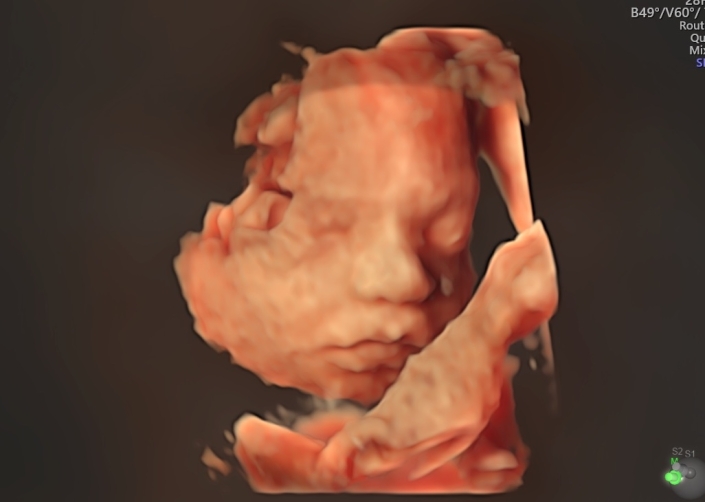

Mit dem Voluson E10 ® von GE steht uns ein modernes Hochleistungs-Ultraschallgerät zur Verfügung.

Das Voluson E10 ®, ein Produkt der GE-Expert-Serie, wurde speziell für die fortschrittliche und subtile Feindiagnostik in Gynäkologie und Pränatalmedizin entwickelt. Wo komplexe Fälle nicht die Ausnahme, sondern die Regel sind. Wo schwierige diagnostische Fragen tagtäglich zu lösen sind. Wo Patienten eine umfassende Information und Beratung erwarten.